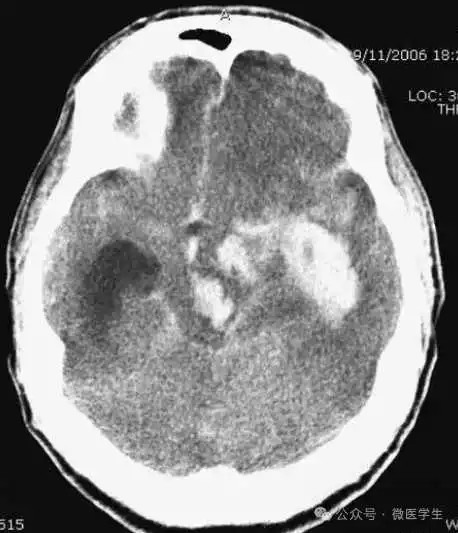

急诊患者的症状大多由于病变的占位效应所引起。能引起脑水肿及占位效应的病变有:原发肿瘤或转移瘤,血管畸形,炎性病变(弓形虫、脑脓肿)。

本例:肿瘤密度较高,邻近大脑镰,周围可见大片低密度水肿区。